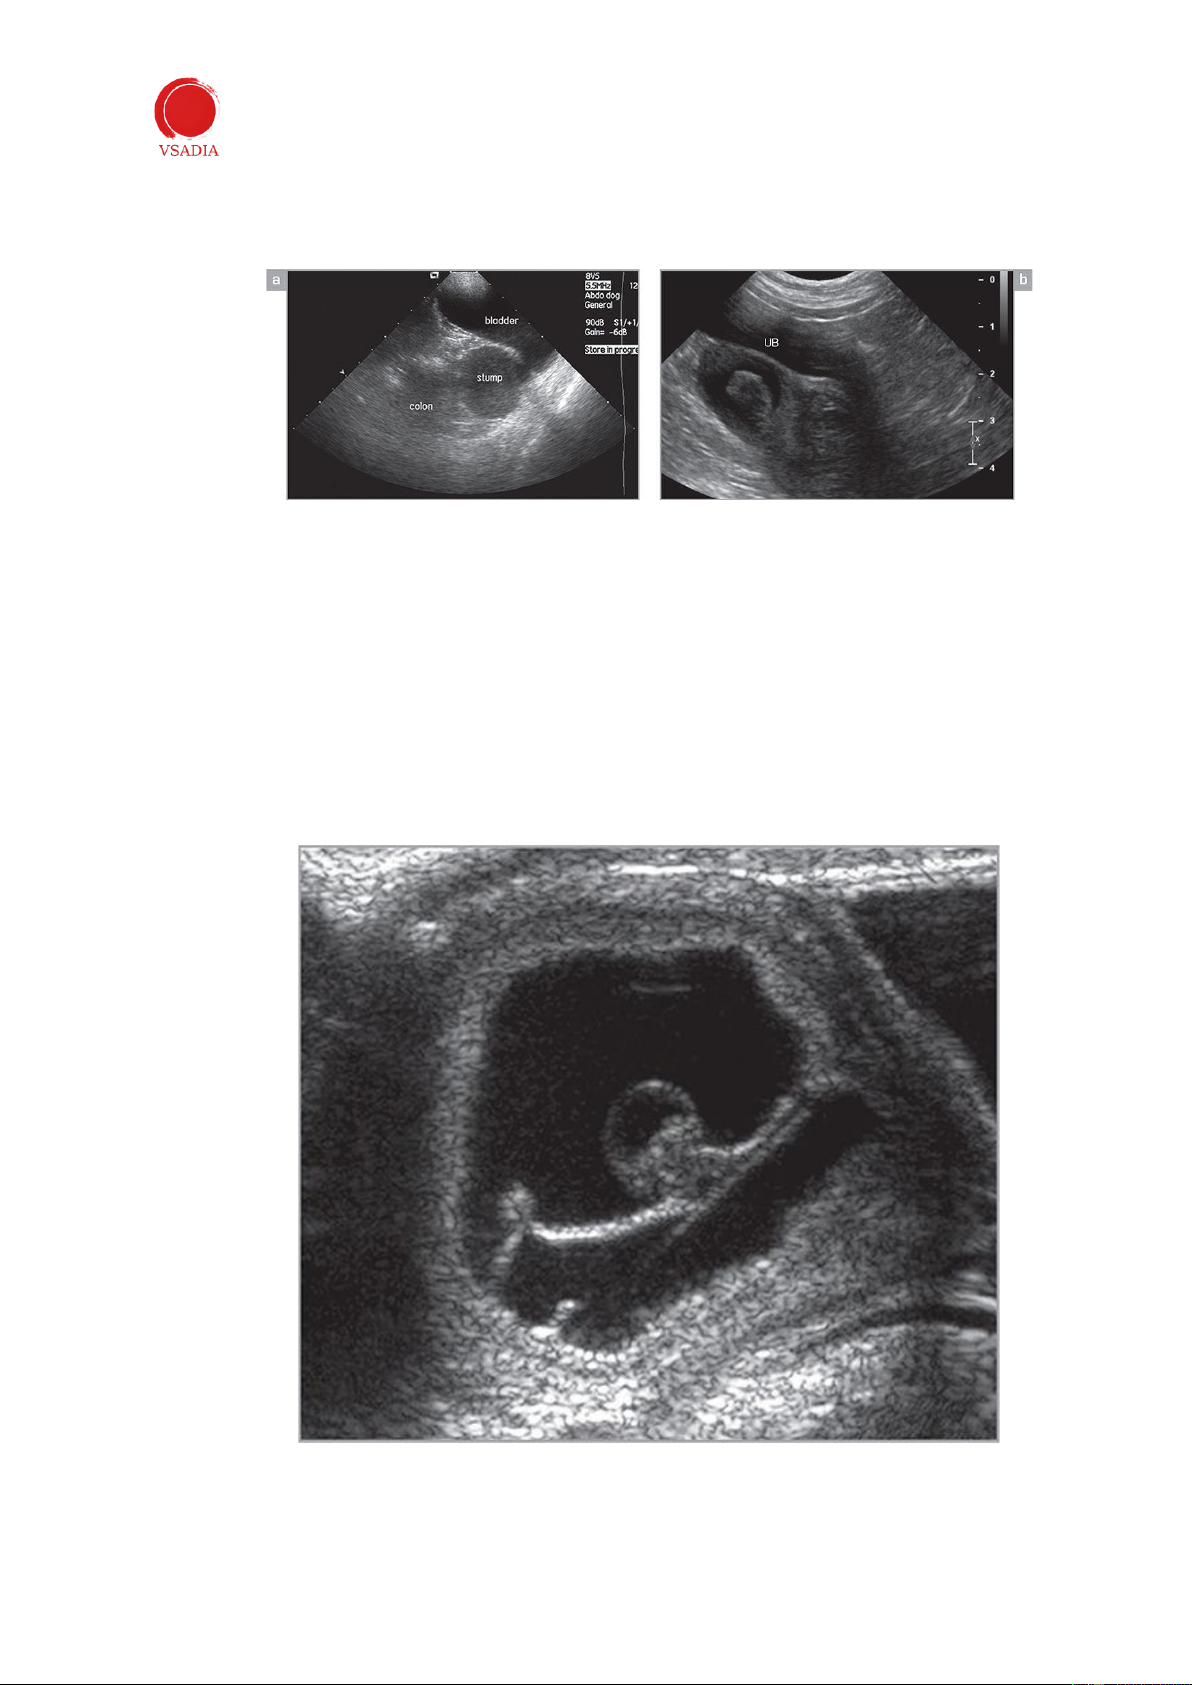

Hình 6: Hình ảnh dọc (a) và ngang (b) của cuống tử cung (*) ở chó lai đã được triệt sản. Gốc tử cung được nhìn

thấy ở phía sau bàng quang. UB: bàng quang tiết niệu; C: đại tràng. -

Khi đã xác định được tử cung, đầu dò sẽ xoay 90° theo chiều kim đồng hồ để đánh giá

cơ quan theo chiều dọc (Hình 6a). -